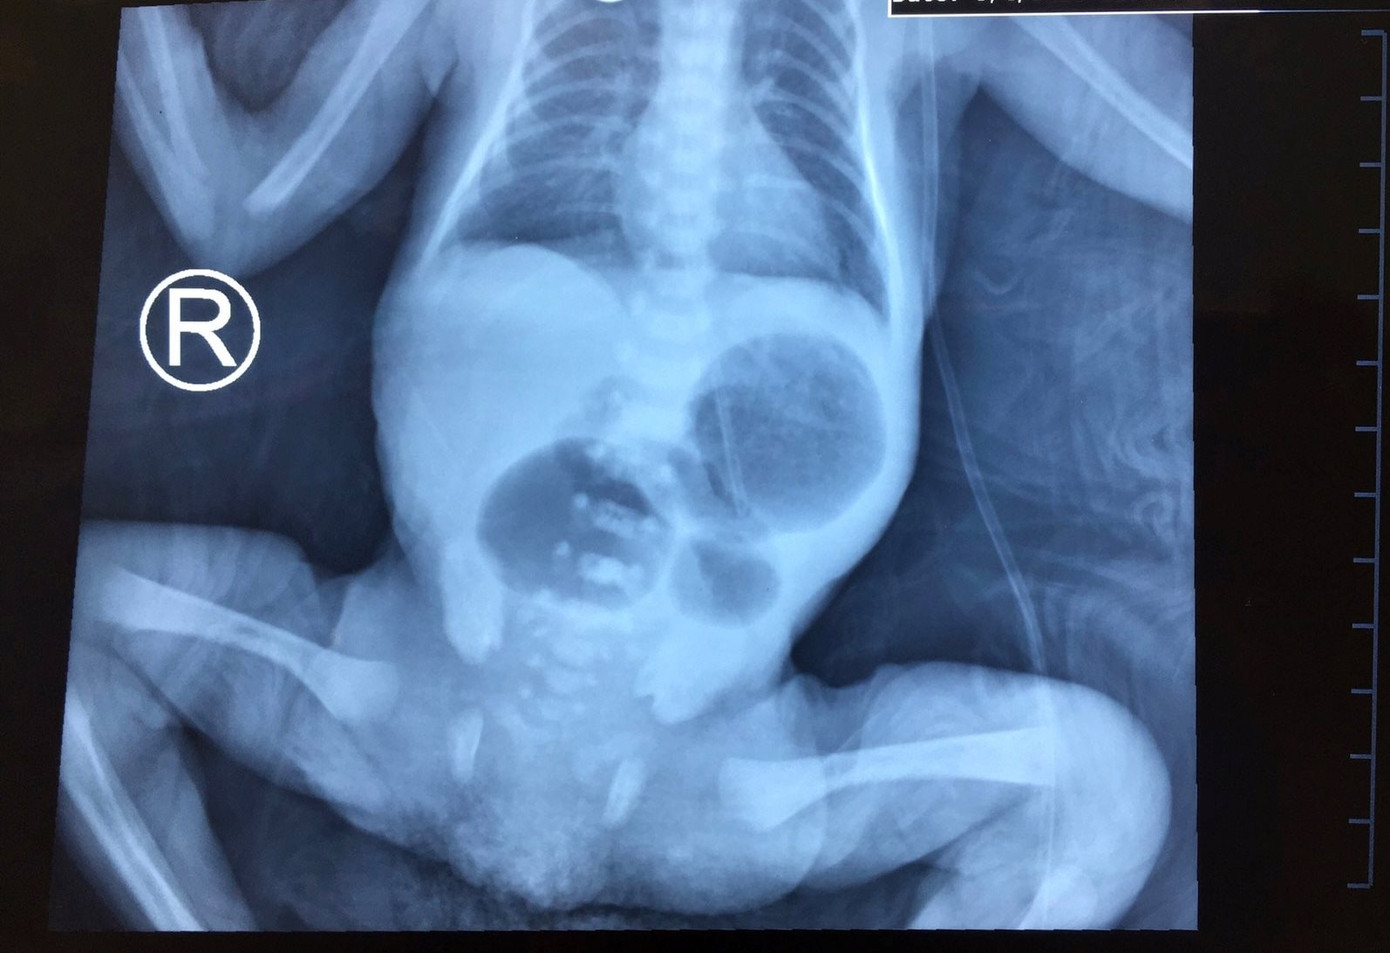

Ngày 8/5, BV Nhi đồng Thành phố cho biết, vừa mổ khẩn, khâu nối 4 đoạn ruột tí hon vừa giãn vừa teo, giải quyết thông tắc kịp thời cho bé gái sơ sinh nhỏ ký nhất Việt Nam.

Trước, đó, sản phụ L.T.A (ngụ Quảng Nam) mang thai 29 tuần buộc phải chấm dứt thai kỳ lập tức vì chuyển dạ sanh non, được mổ bắt con và chuyển viện cấp tốc từ BV Hùng Vương qua BV Nhi đồng Thành phố vì bào thai được theo dõi tắc ruột do dị tật teo ruột non từ trong bụng mẹ. BS CK1 Nguyễn Thị Cẩm Xuyên, ê-kip chẩn đoán tiền sản cho biết, bé gái tí hon ngay sau sinh đã trong tình trạng thở yếu, phải thở NCPAP áp lực dương, bụng chướng căng, ọc nhiều dịch xanh và chưa bài tiết phân su.

Cứu sống trẻ sinh non bị tắc ruột ​ ảnh 1Bé gái sơ sinh bị tắc ruột

Các bác sĩ Khoa Hồi Sức Sơ Sinh, Gây mê phối hợp với Khoa Ngoại tổng hợp đã phối hợp khẩn gây mê, phẫu thuật thành công trẻ sơ sinh non tháng 29 tuần, cân nặng 1,2kg. Đánh giá tình trạng trẻ rất nặng, có chỉ định phẫu thuật cấp cứu.